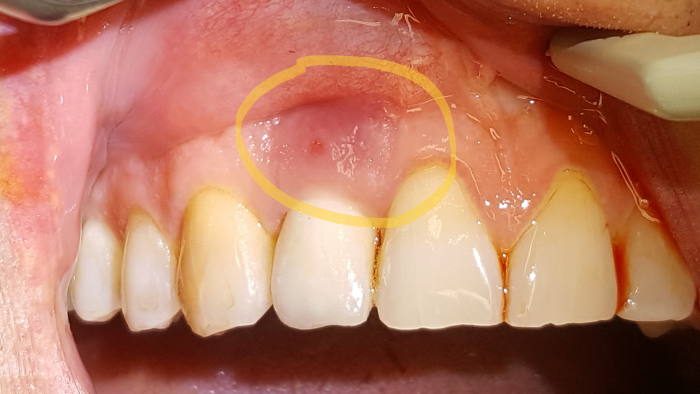

Ienkivut voivat olla myös ihosairauden, palohaavan tai vaikka harjan tai tikun aiheuttamia. Joskus kyseessä on ientulehdus, halkeama hampaan juuressa, märkivä hampaan juuri tai kipeistä lihaksista säteilevä jomotus. Kuvassa näkyy märkivä ien, jonka syyksi paljastui hammasimplantin tulehdus.

Märkivä ien

Myös muut sairaudet voivat säteillä ikenien alueille.